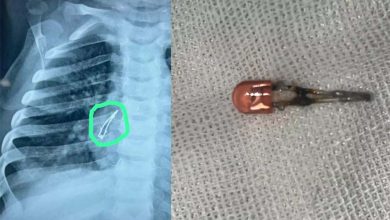

രണ്ടാഴ്ചയോളം ചുമ; ഒന്‍പത് മാസം പ്രായമുള്ള കുഞ്ഞിന്റെ ശ്വാസനാളത്തില്‍നിന്ന് പുറത്തെടുത്തത് എല്‍ഇഡി ബള്‍ബ്

ഗാന്ധിനഗര്‍: ഒന്‍പത് മാസം പ്രായമുള്ള കുഞ്ഞ് അബദ്ധത്തില്‍ വിഴുങ്ങിയ എല്‍ഇഡി ബള്‍ബ് ഓപ്പറേഷനിലൂടെ പുറത്തെടുത്തു. ഗുജറാത്തിലെ അഹമ്മദാബാദിലായിരുന്നു സംഭവം. രണ്ടാഴ്ചത്തോളം ചുമ മാറാത്തത് കൊണ്ടാണ് മുഹമ്മദ് എന്ന് പേരുള്ള കുട്ടിയെ അഹമ്മദാബാദ് സിവില്‍ ആശുപത്രിയില്‍ പ്രവേശിപ്പിച്ചത്. ജുനഗഡിലെ ഒരു ശിശുരോഗ വിദഗ്ദ്ധനെയാണ് കുട്ടിയുടെ മാതാപിതാക്കള്‍ ആദ്യം സമീപിച്ചത്. അദ്ദേഹം തുടര്‍ ചികിത്സയ്ക്കായി ആശുപത്രിയിലേക്ക് റഫര്‍ ചെയ്യുകയായിരുന്നു. അവിടെ നടത്തിയ പരിശോധനയിലാണ് കുഞ്ഞിന്റെ ശ്വാസനാളത്തില്‍ എല്‍ഇഡി ബള്‍ബ് കണ്ടെത്തിയത്. പിന്നീട് ബ്രോങ്കോസ്‌കോപ്പി നടത്തി കുഞ്ഞിന്റെ ശ്വാസനാളത്തില്‍ നിന്ന് ബള്‍ബ് നീക്കം ചെയ്തു. കുട്ടി ആരോഗ്യവാനായിരിക്കുന്നു എന്നും ഉടന്‍ ആശുപത്രി വിടുമെന്നും അധികൃതര്‍ അറിയിച്ചു. കുട്ടി കളിപ്പാട്ടം ഉപയോഗിച്ച് കളിക്കുമ്പോഴാണ് സംഭവം നടന്നതെന്ന് മാതാപിതാക്കള്‍ പറഞ്ഞു. എല്‍ഇഡി ബള്‍ബ് വേര്‍പെട്ട് അബദ്ധത്തില്‍ ഇത് വിഴുങ്ങുകയായിരുന്നു. ഇത് ചുമയ്ക്കും അസ്വസ്ഥതകള്‍ക്കും കാരണമാവുകയായിരുന്നു. കുട്ടികളില്‍ അസാധാരണമായ ലക്ഷണങ്ങള്‍ കാണിക്കുമ്പോള്‍, പ്രത്യേകിച്ച് എന്തെങ്കിലും വിഴുങ്ങിയത് സംശയം തോന്നിയാല്‍ ഉടനടി വൈദ്യസഹായം തേടണമെന്ന് ഡോക്ടര്‍മാര്‍ പറഞ്ഞു.